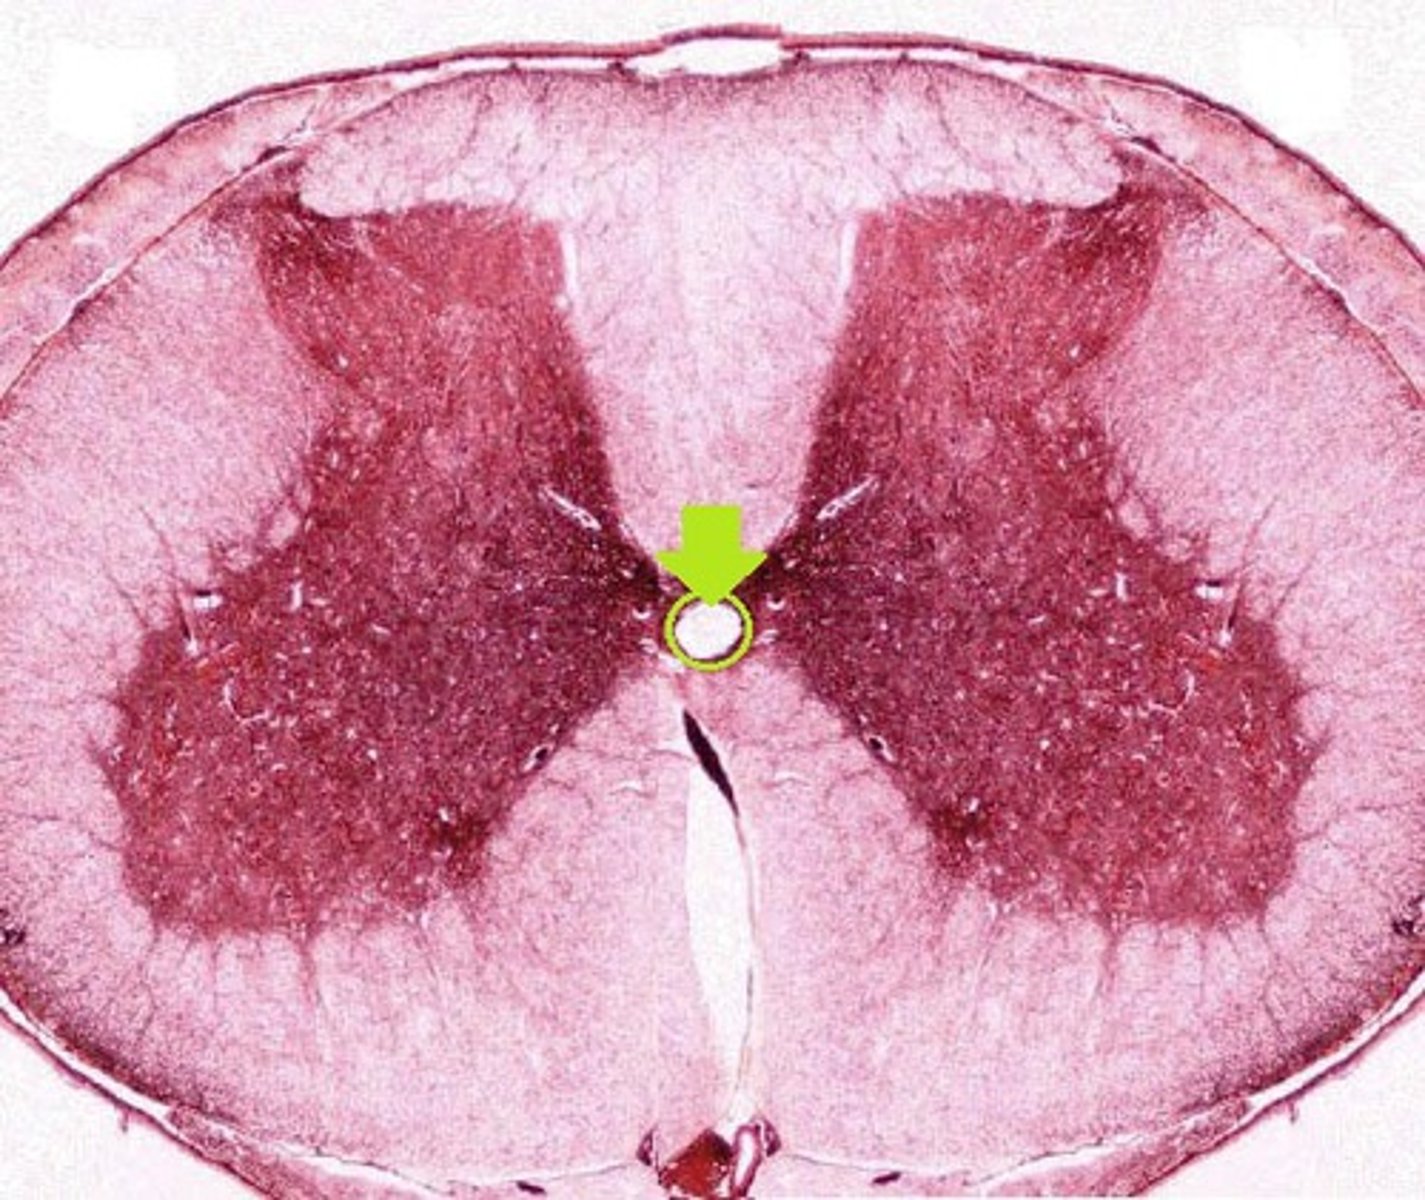

gray commissure

central canal